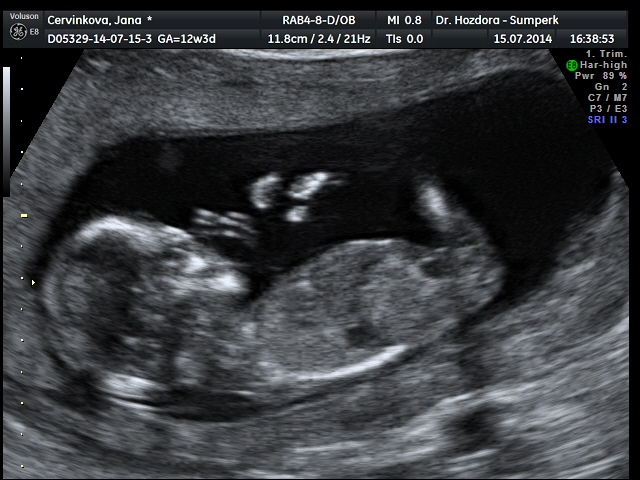

Děvčata srdečně zdravím...genetický ultrazvuk dopadl skvěle.....zítra se dozvím výsledky krevních testů a podle toho se rozhodnu,zda podstoupím nabízenou amniocentézu či ne. Pravděpodobně mám v bříšku holčičku,ale jistější to bude ve 20tt. dostala jsem flešku s obrázkama a kraťoučkým videem,za 3d fotečku jsem si připlatila. Doprovázel mě můj drahoušek a byl z toho docela paf. Mimčo bylo akční.....podle ultrazvuku mám velmi dobrý pocit a věřím,že výsledky budou v pořádku celkově. Jsem tak happy.